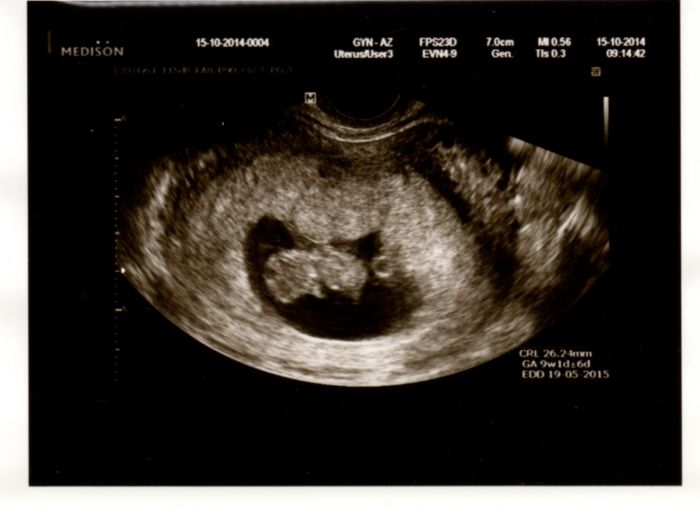

Včera jsem byla na UZ a zatím je všechno v pořádku prcek roste, má 4 cm a srdíčko tlouklo, zrovna si cucalo paleček

Tak se také přidávám s kontrolou. Včera jsem byla u doktora. Zatím je vše v pořádku. Dnes jsem 9+2. Prcek má necelé 3 cm. Srdíčko krásně tluče, tak mám radost. Na screening už jsem konečně také objednaná. 30.10. jdu na krev a pak 12.11. na UZ. Tak už abych to měla za sebou. A konečne jsem také dostala fotečku